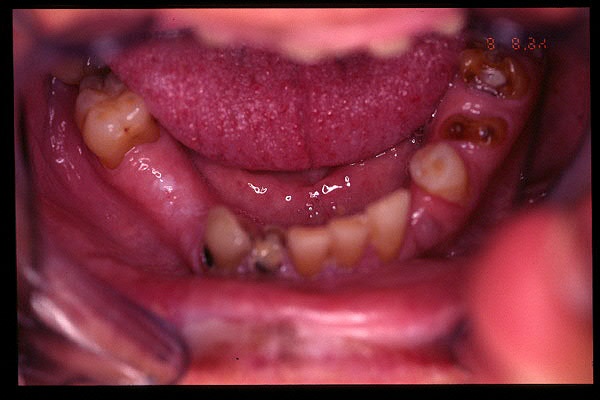

CM Extrusión de incisivos inferiores por falta de contactos oclusales